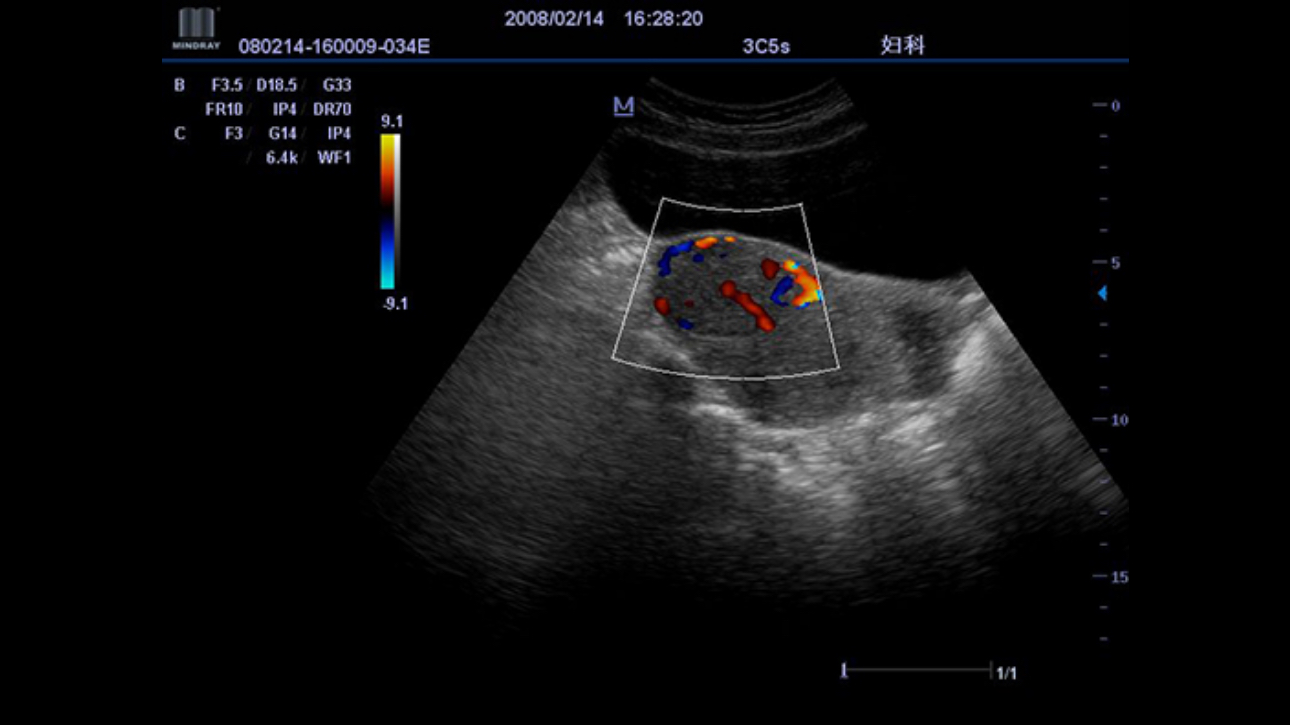

Permits use of multiple scanned angles to form a single image, resulting in enhanced contrast resolution and improved visualization.